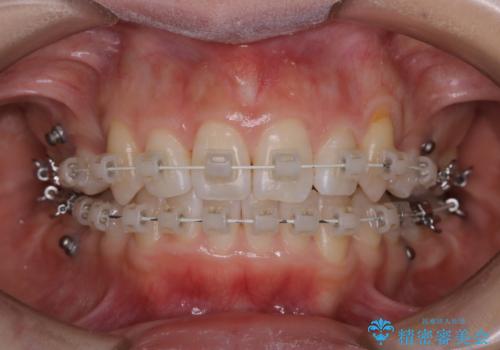

ワイヤー矯正中のPMTC

- ワイヤー矯正中に装置の周りの着色が気になるとのことで来院されました。PMTC30分コースを行いました。

ワイヤー矯正中も、歯の表面に着色(ステイン)が付着することがあります。着色(ステイン)が付着したままだと審美的な問題以外にも、虫歯を発見しずらいことや、細菌が繫殖しやすくなることがあります。クリーニングを行うことで、虫歯や歯周病予防に効果的だったり、もちろん見た目も審美的です。クリーニング後には、汚れが取り除かれ、お口の中がスッキリ・爽快感で気持ちがよくなります。矯正中も定期的にPMTCを行うことが大切です。